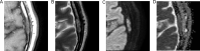

Metaplastic meningioma is a rare World Health Organization Grade I meningioma subtype, accounting for 0.2%-1.6% of all meningiomas. Primary extradural meningiomas represent less than 2% of all meningiomas, with intraosseous meningioma as a subtype of primary extradural meningiomas. Herein, we report the case of a 65-year-old male presenting with headache. His computed tomography scans showed an osteolytic left parietal bone mass, and magnetic resonance imaging revealed hyperintense dots in the mass on T1-weighted images. The mass was then resected and diagnosed on histopathological examination as an intraosseous metaplastic meningioma.